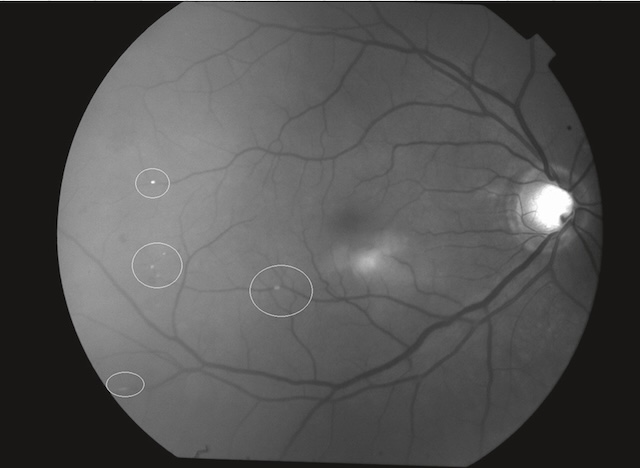

291Beaucoup plus rarement, il s’agit d’emboles lipidiques consécutifs à une fracture des os longs (« embolie graisseuse » se traduisant à l’examen du fond d’œil par des nodules cotonneux, fig. 16.9) ou d’emboles tumoraux (myxome de l’oreillette).

Lésions de petite taille, blanches, superficielles, d’aspect duveteux et à contours flous; chaque nodule correspond à une interruption du flux axoplasmique dans les fibres optiques secondaire à l’occlusion d’une artériole précapillaire. Il s’agit donc d’un signe d’ischémie localisée.

Ces deux photographies couleur du fond d’œil montrent plusieurs nodules cotonneux bien visibles, localisés à proximité de la papille optique. Sur l’image supérieure, les lésions blanches sont groupées en amas irréguliers le long des arcades vasculaires, contrastant nettement avec la rétine environnante. L’image inférieure confirme cette atteinte, avec des foyers cotonneux plus nombreux, éparpillés au-dessus et en dessous de la tête du nerf optique. L’aspect floconneux et blanchâtre de ces nodules traduit une ischémie focale des fibres nerveuses rétiniennes, fréquemment observée dans les rétinopathies hypertensives ou diabétiques.